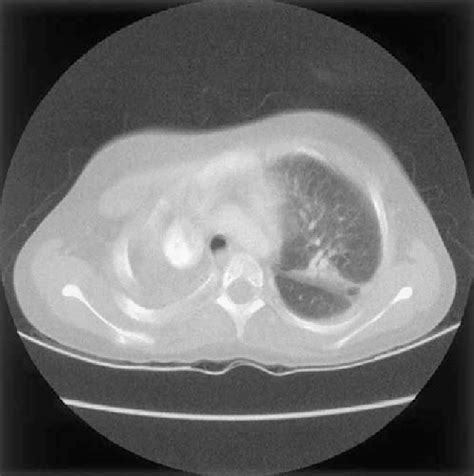

Diagnosing Nocardia Infections: The Detective Work